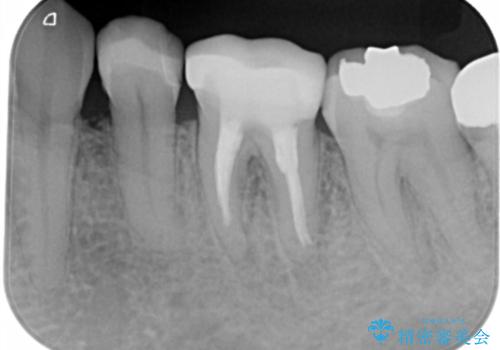

- 左下5番の銀歯をセラミックにやり変え希望の患者様です。

切削量を考慮し、セラミックインレーでの治療を選択しました。

銀歯直下のう蝕を除去しCRで裏層を行った上で、形成・印象を行っています。